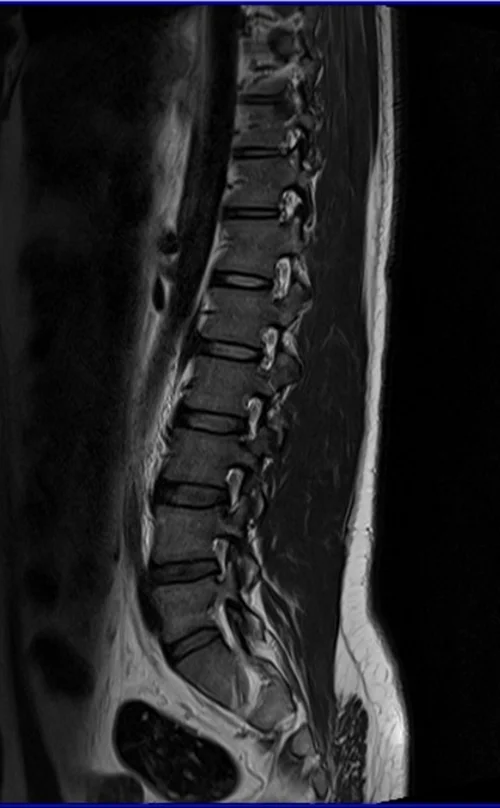

l spine sag t2 image 3 (1) - MRI